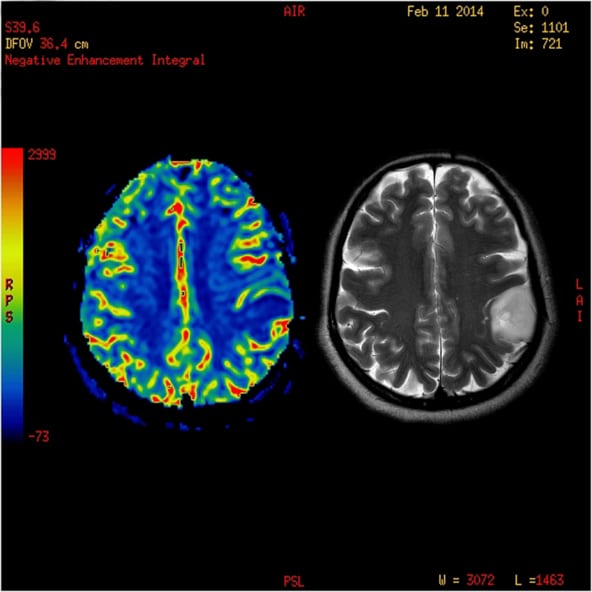

Diagnostic tests for brain cancer involve a history, physical exam, and usually a CT or MRI brain imaging procedure; sometimes a brain tissue biopsy is done.